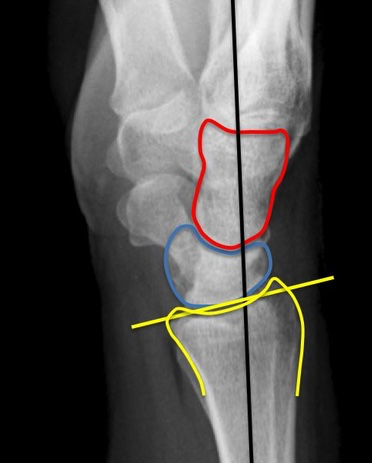

Luxation du Lunatum

- Sur dorsilexion

- Le lunatum perd son articulation avec le radius + hamatum

Luxation Périlunaire

- Sur dorsiflexion aussi

- Le lunatum garde son articulation avec le radius

- L’hamatum perd son articulation avec le lunatum et son alignement avec le Radius

- Scaphoide fracture associée ++